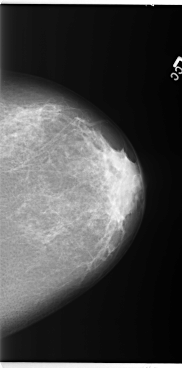

B_3095_1.LEFT_CC

LEFT_CC LINES 5880 PIXELS_PER_LINE 2912 BITS_PER_PIXEL 12 RESOLUTION 50 NON_OVERLAY